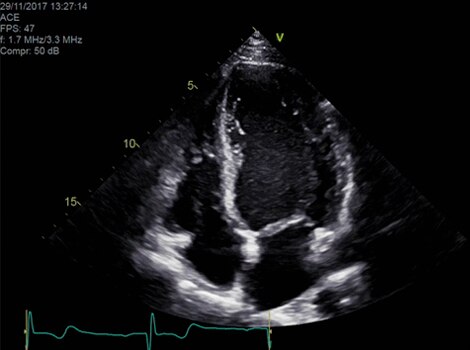

Vivid E95

cSound™ beamforming technology for exceptional visualization quality with impressive resolution in 2D, color flow, Doppler and 4D formats. Read More

VividTM Family Cardiac Ultrasound Automated Function Imaging (AFI)

Assess left ventricular function and cardiac performance with clarity, improving clinical confidence. Read More

Vivid Family Cardiac Ultrasound

Vivid E95 with cSound performance makes 4D as easy as 2D to quantify left ventricular wall motion. Read More

Due to the high mortality rates by the time patients are symptomatic, it is important to identify patients at risk, even when they are asymptomatic. Echocardiography can identify issues or abnormalities related to Aortic Valve structure and function.3

Vivid E95/E90/S70N

Vivid™ Family Cardiac Ultrasound with Automated Quantification

Assess left ventricular function and cardiac performance with clarty,improving clinical confidence.Read More